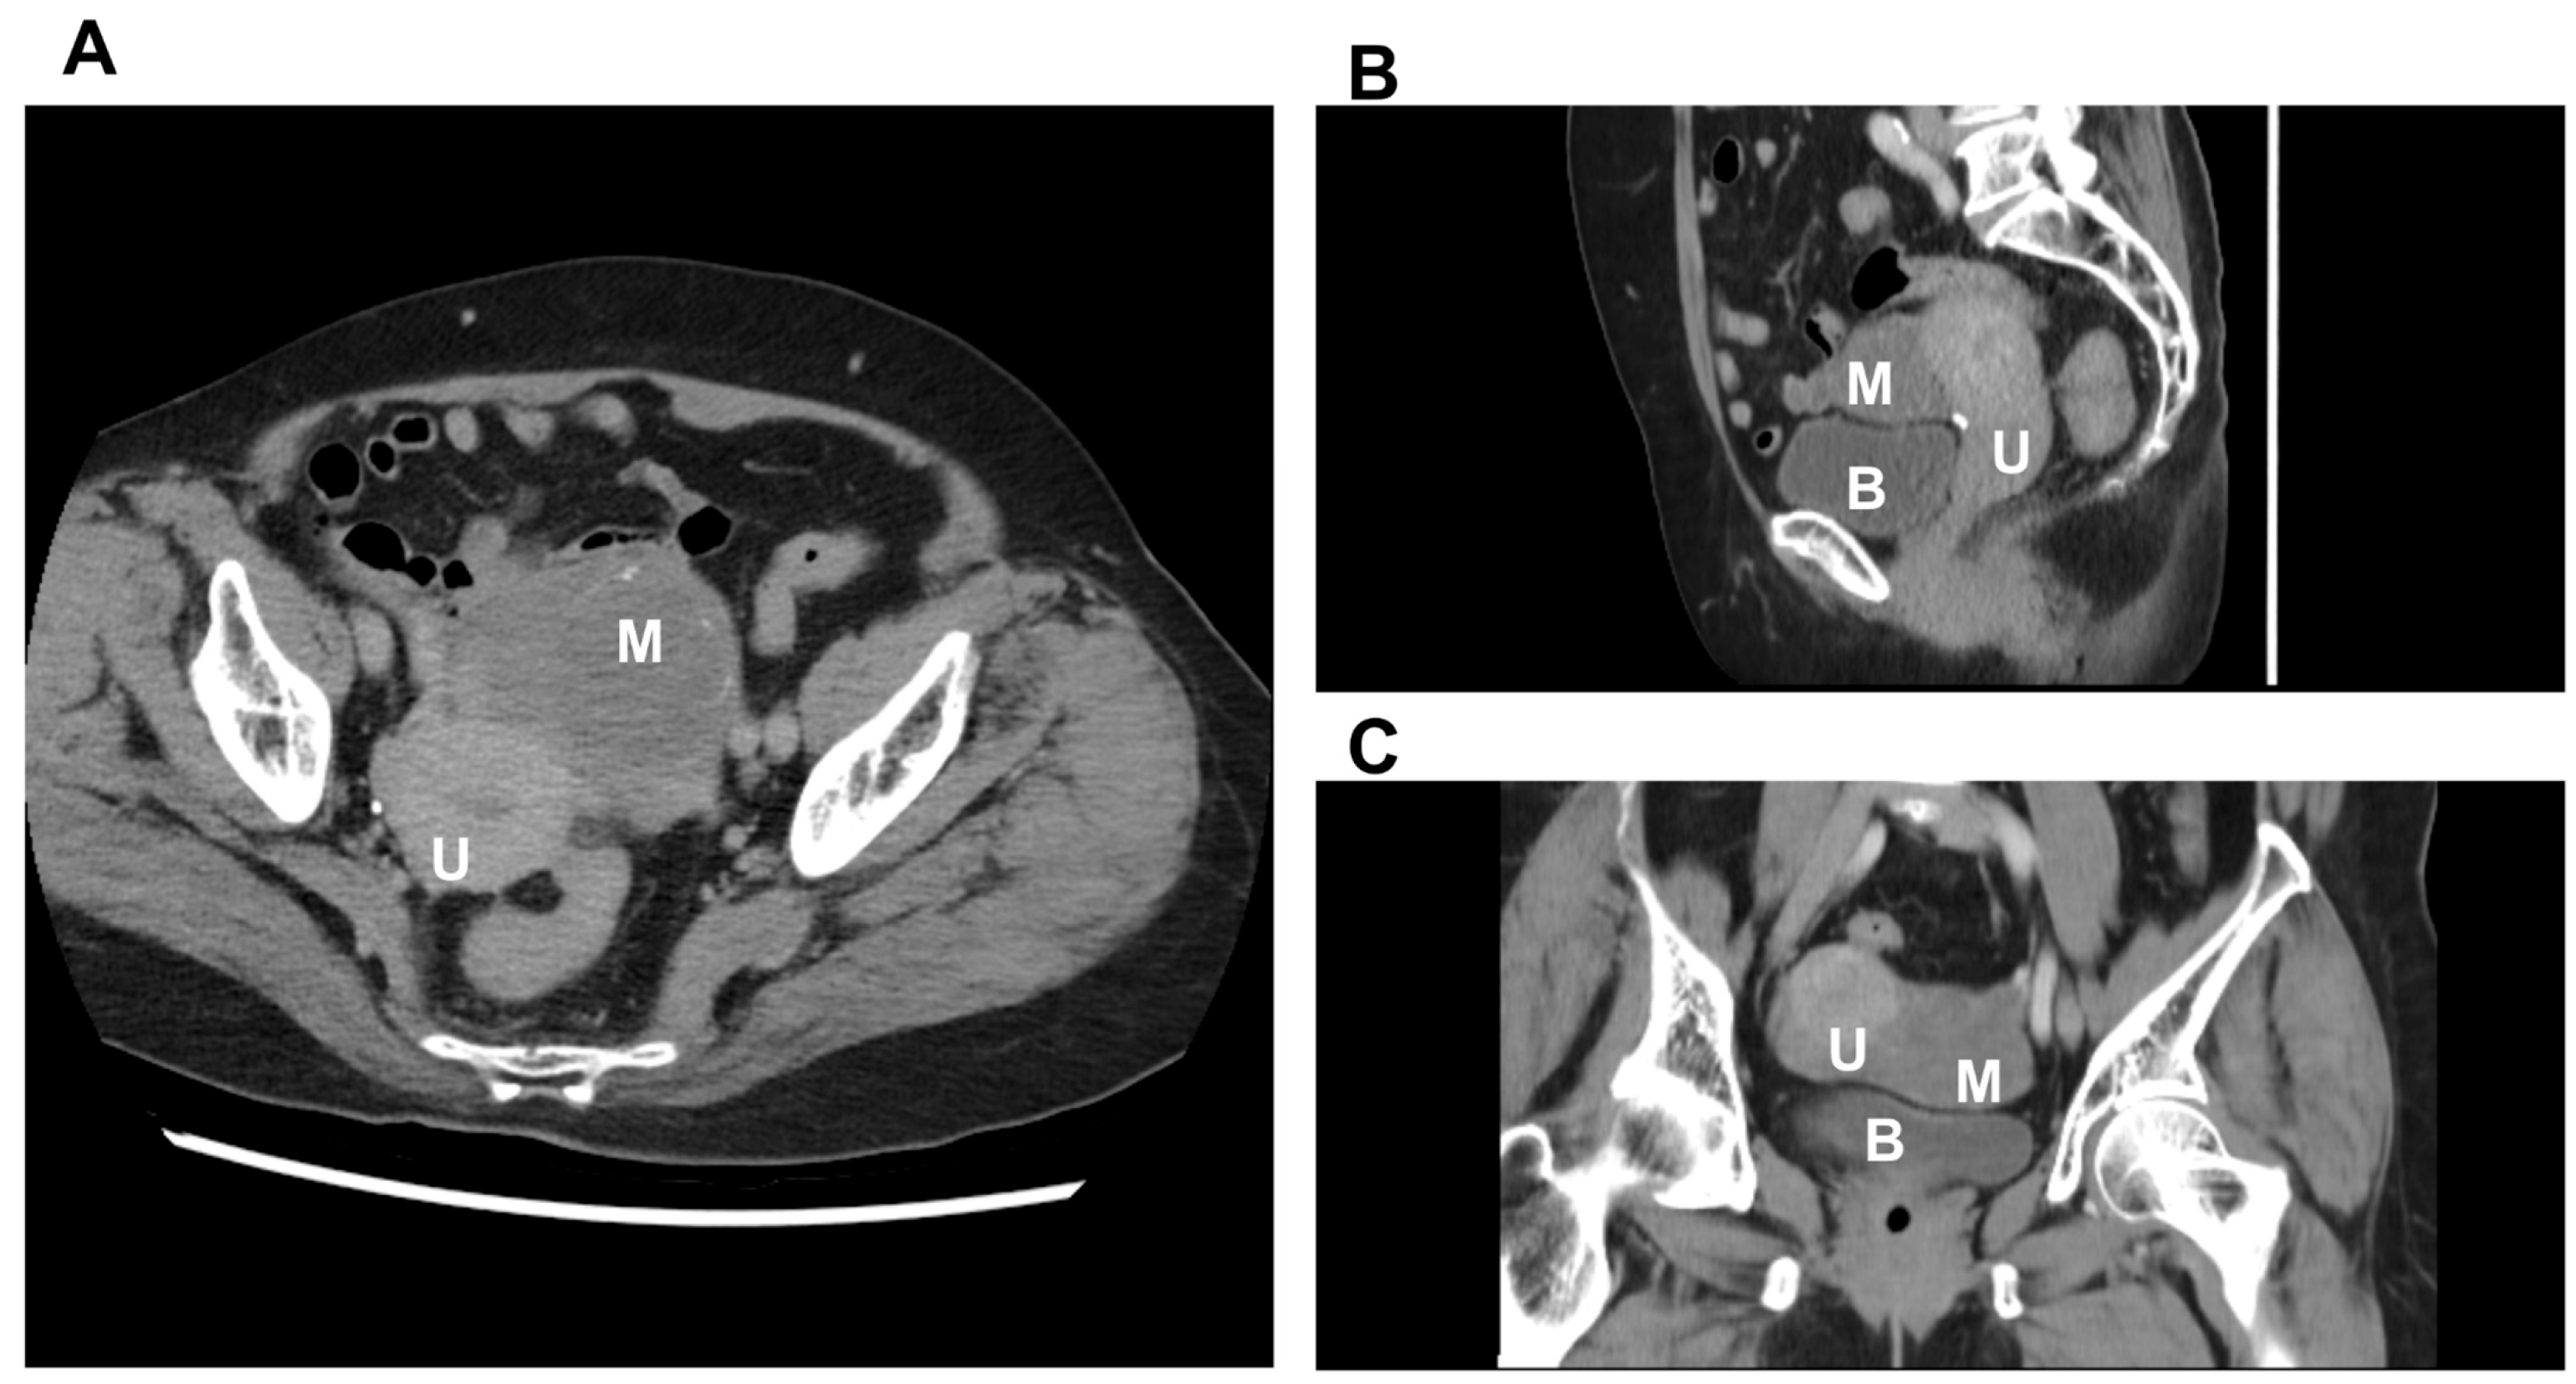

| Present case | 72 years | Postmenopausal spotting, incidental IUD finding | Left paratubal region; 9.0 × 4.54 × 6.37 cm | Solid mass with calcification on US/CT, mimicking an ovarian malignancy | LTH + BSO; uneventful recovery | Leiomyoma with hyalinization, SMA (+), calretinin (−), inhibin (−) |

| CT scan | Useful for acute settings, complication evaluations, and malignancy staging | Detects adnexal masses, hydrosalpinges, pyosalpinges, TOAs, and torsion indicators (U-/C-shaped tube) | Poor discrimination between tubal vs. ovarian tumors; nonspecific for benign vs. malignant; not preferred for initial diagnosis |